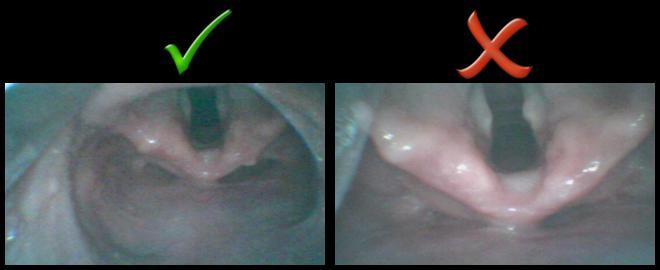

A common mistake many new VL users will make is placing the end of the scope too close to the glottis. When this happens, the end of the scope will actually get in the way of the tip of the ETT as you try to navigate it into the glottis. Instead, back the scope away from the glottis. With VL, it can be preferential to have a grade 2 view over a grade 1 view. This allows a wider field of view and more room to maneuver the tip of the ETT.